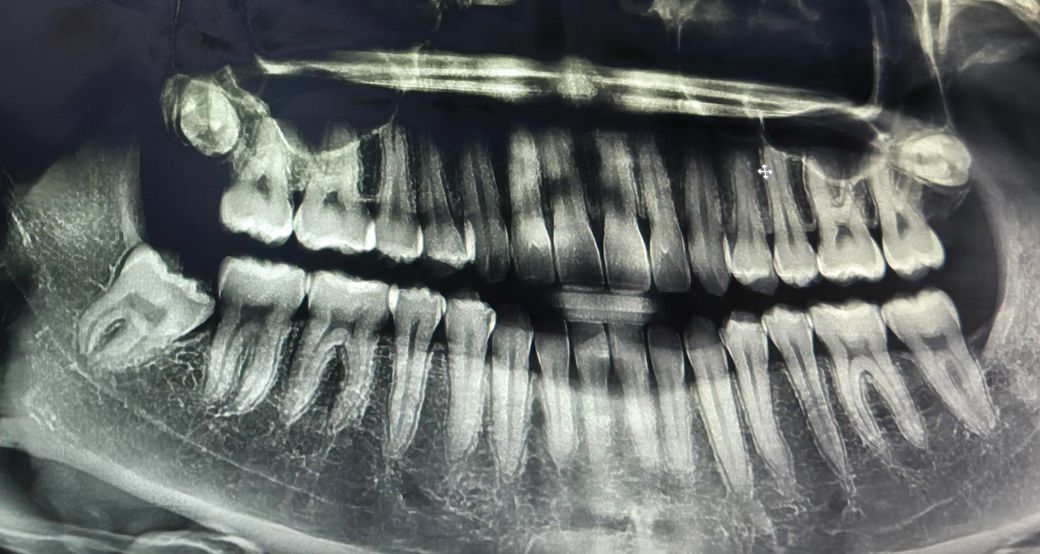

25살 잇몸뼈 상태 심각한가요???

첫번째 치과에서는 잇몸뼈만 조금 내려갔다고 하고 염증이나 충치도 아예 없고 아래앞니쪽 치석이 있는 편이니 스케일링만 받으면 된다고 했어요.

질문 1번. 25살 치고 잇몸뼈 상태가 많이 안 좋은 편인가요? 신경치료할까봐 너무 두렵습니다.

• 3번 째 사진

사진으로 봤을 경우에는 크게 문제가 되어 보이지는 않습니다. 치아는 지금처럼 관리를 잘 해주면 될것으로 생각됩니다.

25살 치고 잇몸뼈 상태가 안 좋은 편은 맞으며 불편한 느낌이 계속 드는 경우 가보시는 게 좋습니다.

다른 치아들의 잇몸뼈는 괜찮은데 앞니의 경우는 잇몸뼈가 나이에 비해서 많이 내려간거 같습니다. 정기적으로 치과를 다니면서 관리를 받으시는게 좋을것같습니다.